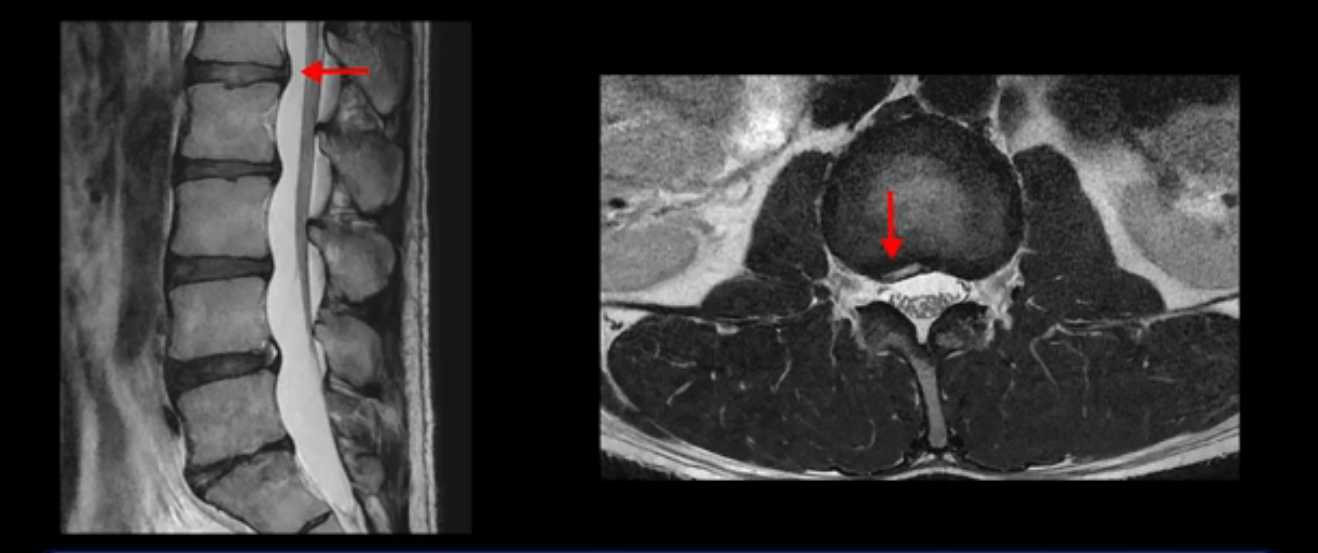

그런데 이분의 증상과 MRI가 전혀 일치하지 않는데, 왜 그런지 지금부터 자세히 설명드립니다. 이분 증상은 앉으면 엉치와 허리가 심하게 아파 10분 이상 앉는 게 어렵고 양쪽 발가락이 앉아있을 때나 누워있을 때 다 저립니다. 걸을 때도 아파서 10분 걷기도 어렵습니다. MRI를 마디마디 살펴보면 1번 2번은 오른쪽으로 살짝 밀려나온 디스크가 있지만 전혀 심하지 않고, 뒤에 또 설명하겠지만 최근에 밀려나온 급성 디스크가 아니고 오래된 디스크로 판단됩니다.

5번 1번 역시 가운데로 디스크 조금 밀려 나와있지만 신경 공간 넓이는 아주 넓어서 신경 눌림 있을 거라고 예상이 안됩니다.

추간공도 보시다시피 왼쪽, 오른쪽 전부 다 매우 넓어서 신경이 눌릴만한 부분이 전혀 보이지 않습니다.